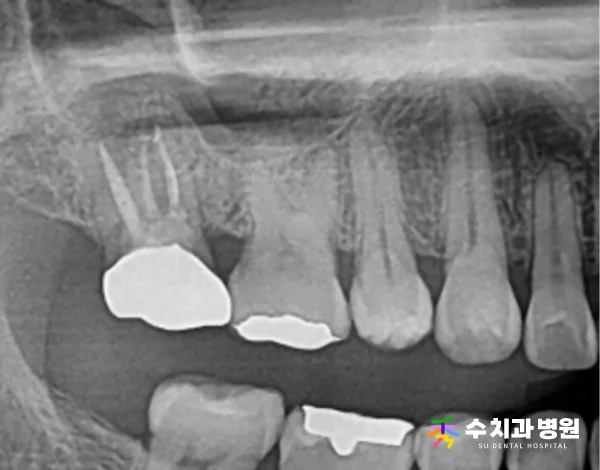

⏱️ 치료 후 경과

치료를 마치고 9개월이 지난 시점에

방사선 검진을 통해 상태를 점검했습니다.

[📸 치료 9개월 후 엑스레이] (촬영일: 2024년 5월)

또한 약 1년 9개월이 경과한 후에도

다시 한번 정기검진을 진행한 결과,

뿌리 끝 염증이 뚜렷하게 호전된 것을 확인했습니다.

[📸 치료 1년 9개월 후 엑스레이] (촬영일: 2025년 5월)

재감염 소견 없이 주변 잇몸뼈가

아주 안정적으로 잘 유지되고 있습니다.